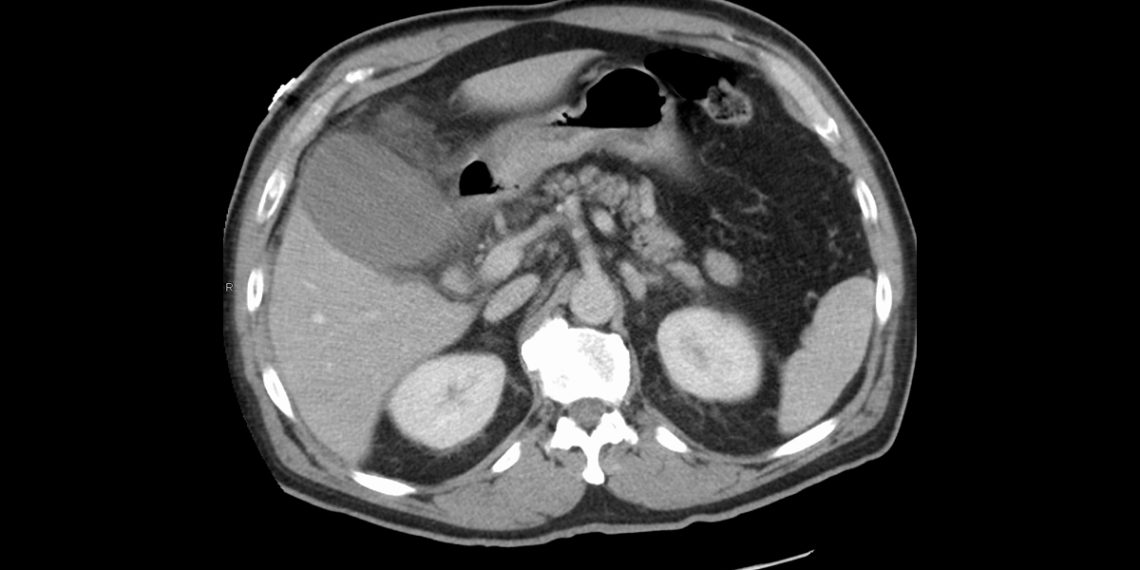

Complications and Long-Term Outlook of Acute Cholecystitis

If not treated promptly, acute cholecystitis can lead to life-threatening complications. The inflammation may spread, or the gallbladder can rupture.

Potential Complications

• Gallbladder gangrene or perforation

• Abscess formation (empyema)

• Peritonitis (inflammation of the abdominal lining)

• Sepsis

• Chronic cholecystitis, which may cause recurrent attacks

• Fistula formation between the gallbladder and intestine

Long-Term Management

After recovery, patients must:

• Avoid high-fat foods to prevent recurrence

• Manage weight and diabetes if applicable

• Stay hydrated and eat fibre-rich meals

• Regularly monitor liver function if there was prior infection

Can You Live Without a Gallbladder?

Yes. After a cholecystectomy, bile flows directly from the liver into the intestine. Some patients experience mild indigestion or looser stools initially, but most adjust well.

Final Thoughts on Complications and Long-Term Outlook of Acute Cholecystitis

Acute cholecystitis is a treatable but serious condition. In South Africa and globally, early recognition and treatment can prevent major complications. With timely surgery and lifestyle adjustments, patients often recover fully and lead normal lives.